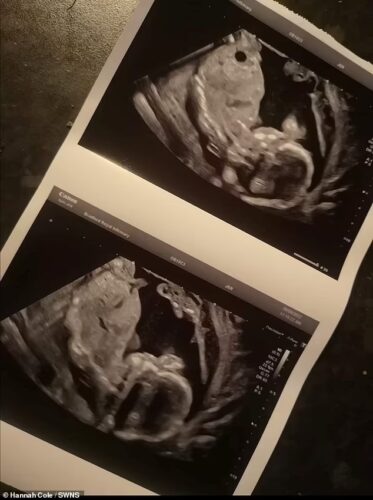

Após insistir com os médicos, Hannah passou por novos exames e aconteceu o que chamou de “Milagre de Natal”. O eletrocardiograma feito ao feto voltou a mostrar o registo de batimentos cardíacos. Só que o bebê ainda não estava pronto para nascer.

Os médicos conseguiram manter o bebê vivo durante mais quatro semanas, até a data em que finalmente optaram por fazer o parto. Oakley nasceu com 24 semanas no dia 30 de outubro. Ele pesava apenas com 780 gramas.